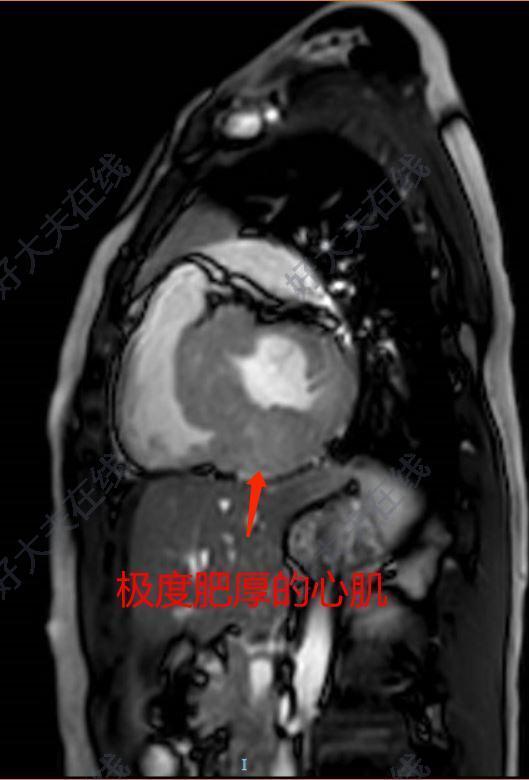

肥厚型心肌?。℉CM):特征為心室壁呈不對稱性肥厚,常侵及室間隔,心室內(nèi)腔變小,左心室血液充盈受阻,左心室舒張期順應(yīng)性下降。肥厚型梗阻性心肌?。℉OCM)是HCM中的一種,以LVOT梗阻為特征。HOCM約占到HCM的1/3,患者表現(xiàn)為呼吸困難、心悸、乏力、頭暈與暈厥、晚期易發(fā)生心力衰竭與猝死。肥厚型梗阻性心肌?。℉OCM)的治療:目前通過射頻消融治療肥厚型梗阻性心肌病是近幾年國內(nèi)外的研究前沿技術(shù),術(shù)中即刻的壓力階差下降程度非常顯著,其主要特點為成功率高,創(chuàng)傷小,并發(fā)癥少,住院時間短,患者舒適度高。結(jié)合心腔內(nèi)超聲三維標測指導(dǎo)射頻消融治療肥厚型梗阻性心肌病治療,由于消融導(dǎo)管能標測希氏束和左束支電位,所以發(fā)生傳導(dǎo)阻滯的風(fēng)險更小,不會造成急性心肌梗死,右束支傳導(dǎo)阻滯。?Cartosound指導(dǎo)下HOCM消融依據(jù):在肥厚性梗阻性心肌病中,部分患者無法耐受外科室間隔切除術(shù)。有5%-15%的患者因無合適的室間隔支,而難以實行酒精化學(xué)消融。射頻消融致局部心肌壞死,失去收縮運動,減少流出道梗阻被消融的組織在水腫逐漸消失后,局部組織出現(xiàn)瘢痕攣縮,減少流出道梗阻?CARTOSOUND直視下肥厚型梗阻性心肌病消融流程:?手術(shù)驗證——壓差實時監(jiān)測結(jié)果:Cartosound指導(dǎo)下HOCM消融優(yōu)勢:⑴精確:精準定位消融靶區(qū)域,如SAM征區(qū)或室間隔最肥厚處⑵安全:標記His-LBB,預(yù)防傳導(dǎo)系統(tǒng)損傷⑶簡單:三維導(dǎo)航,大幅降低手術(shù)難度?該技術(shù)的臨床應(yīng)用意義:肥厚型梗阻性心肌病中國約有90萬患者,患者表現(xiàn)為呼吸困難,心悸,乏力、頭暈與暈厥,易發(fā)生心力衰竭與猝死,該技術(shù)能顯著降低左室流出道壓力階差,緩解患者癥狀,降低心源性猝死風(fēng)險,改善生活質(zhì)量,減輕患者反復(fù)住院帶來的經(jīng)濟損耗,一定程度上減輕社會負擔。且該技術(shù)具有成功率高,創(chuàng)傷小,并發(fā)癥少,住院時間短,患者舒適度高等特點。?專家簡歷:王彬,醫(yī)學(xué)博士,副主任醫(yī)師,就職于空軍軍醫(yī)大學(xué)唐都醫(yī)院心臟內(nèi)科,主要從事冠心病、心律失常診斷及介入治療,在復(fù)雜冠心病介入治療、心律失常射頻消融治療和永久起搏器植入術(shù)方面積累了豐富的臨床經(jīng)驗?,F(xiàn)任中華醫(yī)學(xué)會心電生理與起搏分會、中國醫(yī)師協(xié)會心律學(xué)專業(yè)委員會第一屆中青年電生理工作委員會委員,中國老年保健醫(yī)學(xué)研究會心臟學(xué)會心肺血管委員會委員,陜西省醫(yī)學(xué)會心電生理與起搏分會青年委員會委員。發(fā)表論著22篇,其中SCI收錄4篇,第一作者發(fā)表論著7篇,獲得國家發(fā)明專利1項,實用新型專利7項,參與國家自然科學(xué)基金1項,陜西省自然科學(xué)基金1項。??